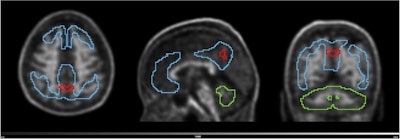

Volume with higher baseline signal for N1 accumulators and N1 non-accumulators of amyloid (red line) overlayed on the scan of an N1 accumulator (MNI space). Grey scale shows SUVR range. Blue line shows the Centiloid target region and the green line shows the reference region (whole cerebellum). Image and caption available for republishing under Creative Commons license (CC BY 4.0 DEED, Attribution 4.0 International) and courtesy of the European Journal of Nuclear Medicine and Molecular Imaging.

The researchers categorized individuals based on baseline Centiloid values (CL) into amyloid positive (CL > 35.7), “gray zone” (20 < CL ≤ 35.7), and amyloid negative (CL ≤ 20) groups. They further split the amyloid negative group into two groups: N1 (CL ≤ 13.5) and N2 (13.5 < CL ≤ 20). Centiloids are voxel (3D pixel) measurements that indicate areas with amyloid deposits, with values based on a 100-point scale.

Finally, in a parametric image analysis of N1 accumulators, a region within the precuneus was linked to increased amyloid over time, the researchers reported.

Nonetheless, the study also validates that the precuneus is a cortical region with early amyloid accumulation in Alzheimer’s disease and that its focal signal can lead to positive visual PET reads on images from patients with low CL values, the group added.